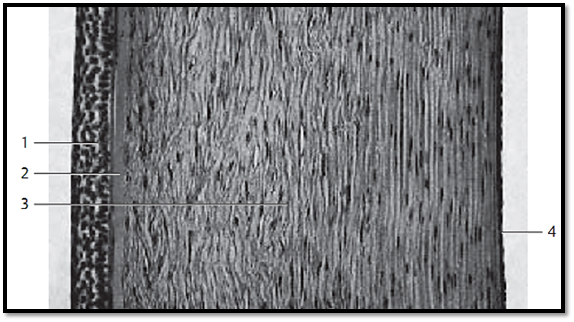

This vertical section through the cornea provides a clear image of the layered structure. The outer covering consists of five or six layers of nonkeratinizing cells (multilayered nonkeratinizing squamous epithelium) 1. It is about 70 μm high and is supported by a basal membrane. The limiting lamina ( Bowman’s membrane ) 2 follows as a relatively wide layer. The thick corneal stroma (substantia propria corneae ) 3 features 20 0–250 densely stacked lamellae about 2 μm thick , with interleaved parallel oriented collagen fibrils. Fibrocytes (keratinocytes ) with cytoplasmic processes (“branched fibrocytes) are found between collagen fibrils. The corneal f ibrocytes appear spindle-shape d in vertical sections. The thinner posterior limiting lamella ( Descemet’s membrane ) separates the corneal stroma from the about 5 μm thick posterior single-layered corneal epithelium (corneal endothelium).

1 Anterior corneal epithelium

2 Anterior limiting lamina, Bowman’s membrane

3 Corneal stroma, substantia propria corneae with fibrocytes (keratinocytes)

4 Posterior corneal epithelium (corneal endothelium)

Stain: alum hematoxylin-eosin; magnification: × 50